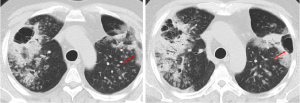

Mycobacterium TB infection

Cavitation is a hallmark of post-primary TB, occurring in approximately 50% of patients (7). The likelihood of cavitation correlates with higher sputum mycobacterial loads (8). Moreover, cavitation is an uncommon feature of primary TB, which is characterized by inflammation and granuloma formation that does not usually lead to the tissue destruction that causes cavitation (8,17). Cavitation primarily occurs in post-primary TB, when the bacteria reactivate from dormant state and the immune system’s response leads to more extensive tissue damage and cavitation (8,17). Hence, radiologically, primary TB is more likely to show intra-thoracic lymph node enlargement, pleural effusion and lower lobe lung lesions. Cavitation is less characteristic of these initial presentations, seen only in 10–30% of cases (17). Typical imaging findings of post-primary TB include a predilection for the upper lobes, particularly the apical and posterior segments (7). Patchy and poorly defined consolidations are often the earliest findings (7,8). Cavities often form within areas of consolidation, exhibiting variable wall thickness, ranging from thin and smooth to thick and nodular walls (Figures 7-9) (8). Air-fluid levels are seen in 10–20% of tuberculous cavities (18). Endobronchial dissemination can lead to tree-in-bud opacities, and pleural effusion is common (8).